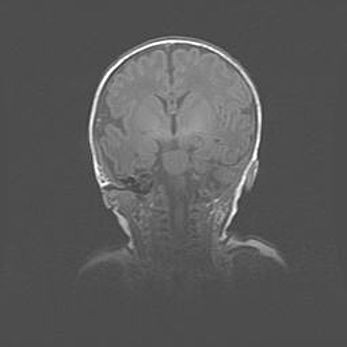

Сообщающаяся гидроцефалия. Кистозная энцефаломаляция головного мозга.

Возраст: 3 месяца 4 дня

Вес: 3100 г

Пол: женский

Окружность головы: 34 см

Срок гестации: 31 неделя

Кистозная энцефаломаляция головного мозга - одна из форм поражения головного мозга в детском возрасте. Характеризуется возникновением множественных и распространённых кист в коре, белом веществе и подкорковых образованиях головного мозга у плодов, новорождённых и детей раннего возраста. Развитие кистозной энцефаломаляции связано с внутриутробной асфиксией и гипотонией, родовой травмой, тромбозом синусов, пороками развития сосудов, инфекциями, сепсисом и другими причинами. Наиболее значимые инфекционные агенты: вирусы простого герпеса, цитомегалии, краснухи, токсоплазмы, энтеробактерии, золотистый стафилококк и другие.